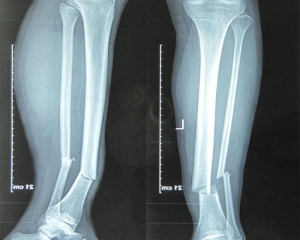

Gãy xương cẳng chân kín: Triệu chứng nhận biết và những điều cần biết

Gãy xương cẳng chân kín là một chấn thương phổ biến, đặc biệt trong các...